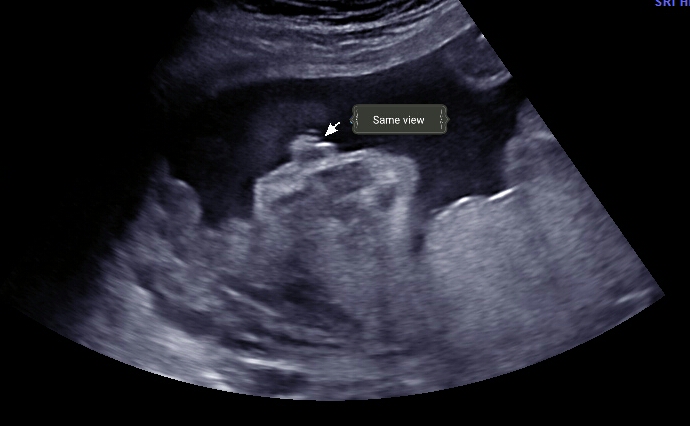

This was 23 weeks taken from the side view as if looking past the under thighs and genitals. Any thoughts?? Thanks!Attachment 39029

Same angle different picture

The tech actually guessed girl....but everyone I've shown has thought boy!

Wait, the tech actually guessed girl?! That second picture looks like a penis and testicles to me... that first one would have to be a PRETTY swollen vulva!

That was my thought! I don't have any more pictures. She only looked at it from this angle for two minutes, no between the legs or under bum angle.